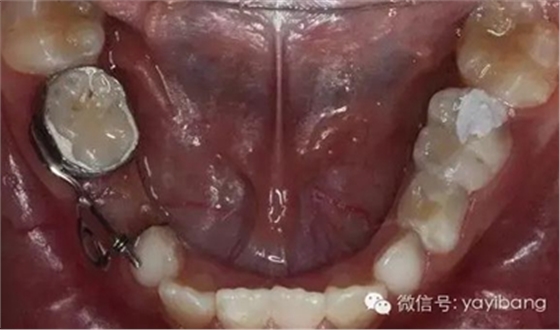

36、放回模型試合,合面觀

39、推簧加力后合面觀

40、加力后,重新就位合面觀